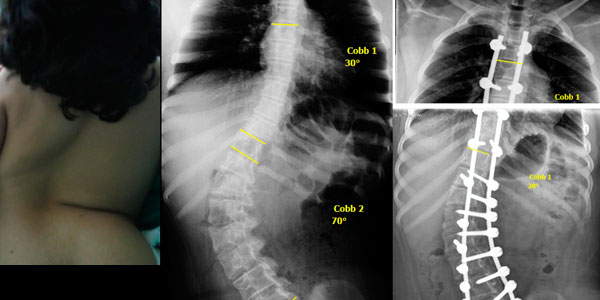

Me diagnosticaron escoliosis cuando tenía 13 años, en el año 2010 y ese mismo año me operaron en el mes de octubre. Al inicio, no me gustó la idea de la operación porque interfería con algunos planes que ya tenía en mente, pero sabía que si quería estar bien, tenía que sacrificarlos porque más importante era mi salud. No muchos doctores saben de esta enfermedad, gracias a Dios conocí al Dr. Cárdenas que fue muy amable y amigable conmigo y me explicó con todo detalle como sería la intervención; así que más que miedo, sentía emoción porque llegara el día.

Después de mi operación, solo estuve internada 4 días. Tengo 11 tornillos en mi columna y ya llevo 5 años de operada; vivo una vida normal y soy feliz.